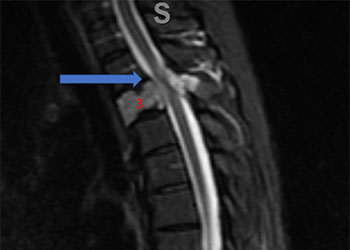

Spine:

Central Cord Syndrome

Author: Yusef Imani M.D., F.A.A.N.S., Read More!